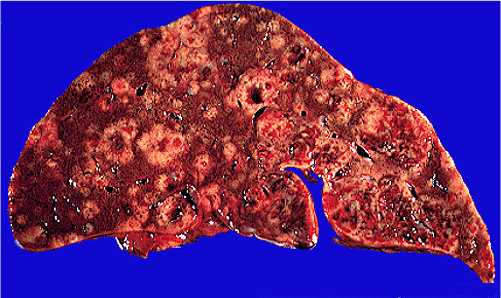

Galactosemia pictures: